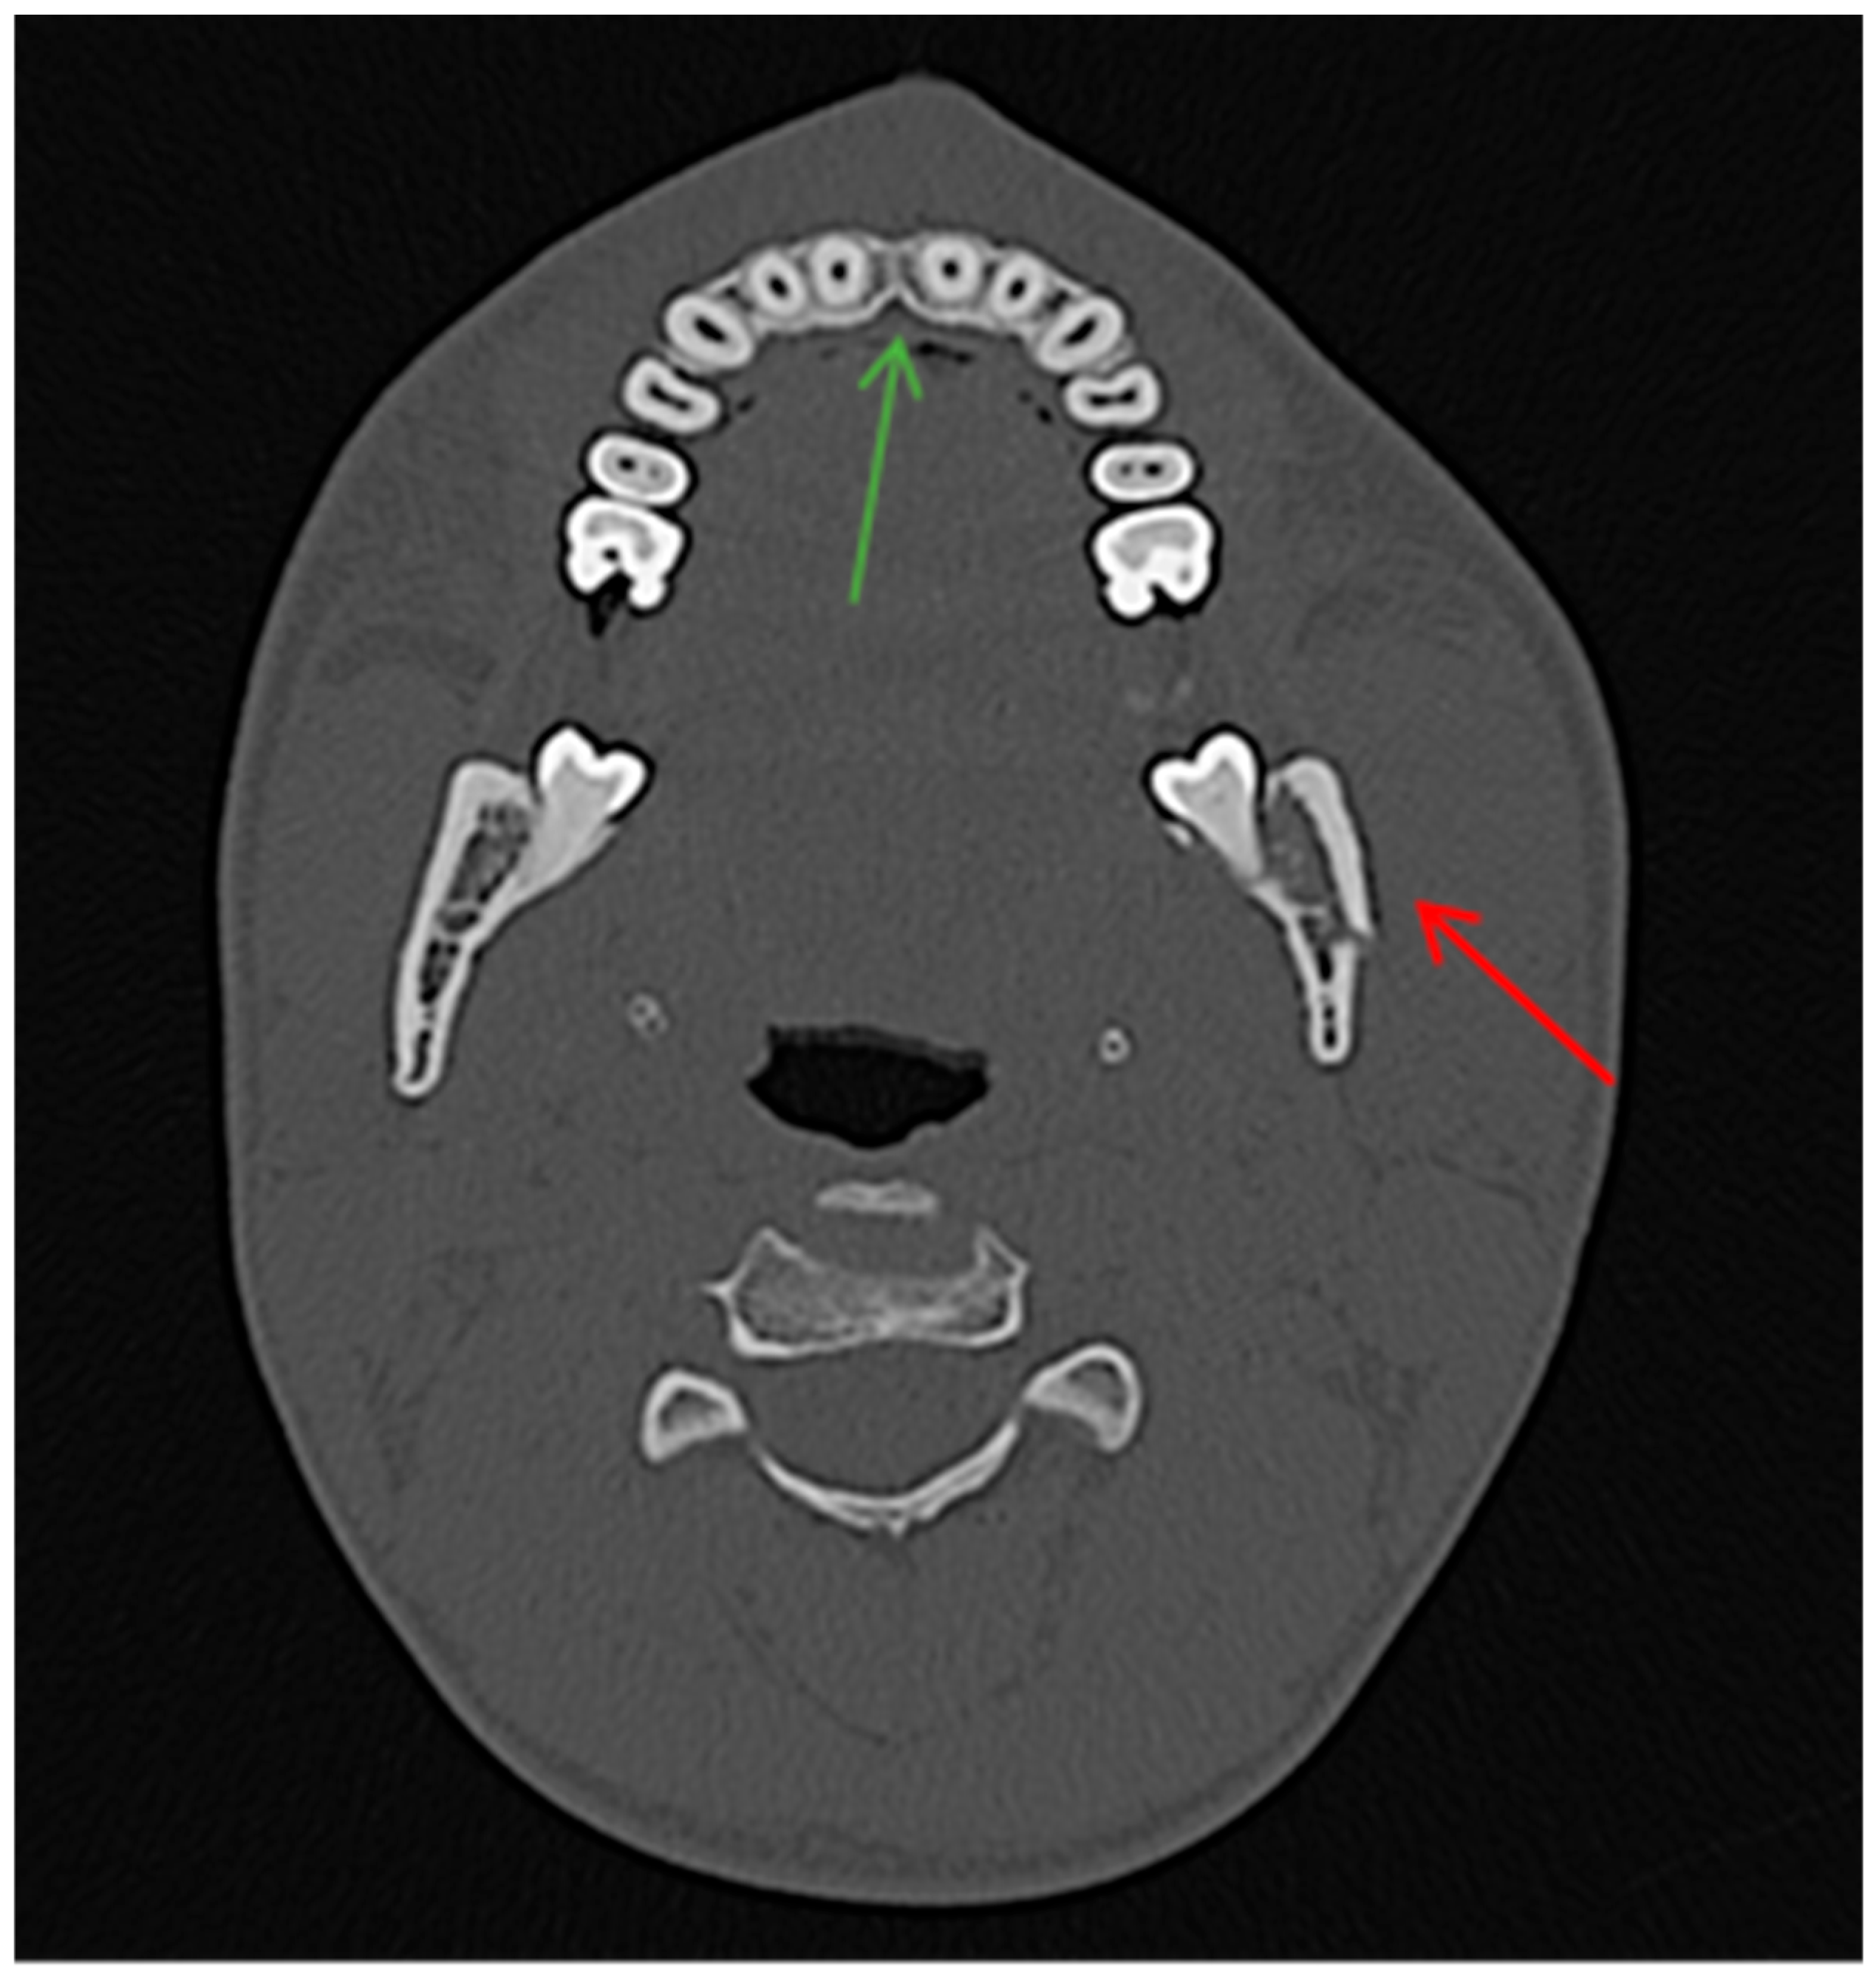

- Open fractures: located within the body/angle of mandible;

- Closed fractures: located within the ramus, condylar/coronoid process of mandible.

- True positive (TP)—diagnosed body/angle fracture + presence of AS in soft tissues.

- True negative (TN)—no body/angle fracture + no AS in soft tissues.

- False negative (FN)—diagnosed body/angle fracture + no AS in soft tissues.